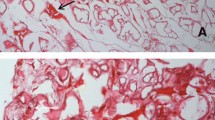

Amyloid has specific structural and staining properties and the gold standard for the diagnosis of amyloidosis is the histological identification of amyloid by the birefringence of Congo Red (CR) stain under polarizing light. Such a typical CR birefringence has been reported to be visible in cartilage (Millucci et al 2012; Spencer et al 2004) and synovia (Millucci et al 2012) from AKU patients (Fig. 1). Remarkably, the amyloid presence was mainly found in correspondence of ochronotic areas and shards, thus suggesting a strict intimate structural correlation between pigment and amyloid (Millucci et al 2012; Spencer et al 2004). Amyloid fibrils appeared as twisted rods composed of cross-beta sheet structures that selectively bound the dye CR and Thioflavin-T, thus this latter fluorescent dye confirmed the presence of amyloid aggregates in cartilage and synovial tissue from AKU patients (Millucci et al 2012). The presence of amyloid deposit was observable also in chondrocytes isolated from ochronotic cartilage of AKU patients (Millucci et al 2012), in keeping with evidence that synoviocytes and chondrocytes may be important producers of amyloid (Momohara et al 2008). Moreover, both synoviocytes and chondrocytes express HGD, thus contributing to the local production of ochronotic pigment and amyloid (Laschi et al 2012).

Congo red staining of amyloid in AKU cartilage (left) and synovia (right). Birefringent amyloid deposits in strongly degenerated AKU articular cartilage (left) were detected, particularly localized in pigmented areas although amyloid infiltrates were evident all throughout the tissue. AKU synovia (right) also showed massive and extensive amyloid infiltration, predominantly in the superficial layer of the synovial membrane, and especially in concomitance with pigmented areas and with ochronotic shards. Local inflammation and tissue damage were evidenced by the presence, in both AKU cartilage and synovia samples, of inflammatory infiltrates, consisting mainly of monocytes and macrophages